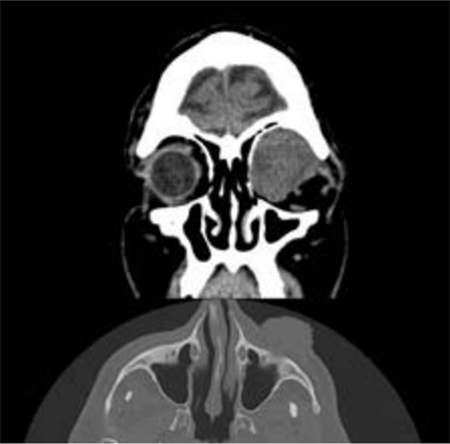

• Se solicita tomografía axial computada (TAC) de órbita con cortes de 3 mm y laboratorio.

• A los 20 días el paciente acude por guardia refiriendo dolor en OI, secreciones purulentas, congestión mixta, absceso corneal inferior, con hipopion 3 mm (figura 2). La agudeza visual (AV) estaba severamente afectada (sin percepción luminosa). Se decide internar al paciente y se realiza interconsulta con infectología, iniciando tratamiento antibiótico de amplio espectro, se solicita TAC de órbita (Fig. 3) y laboratorio de urgencia. Se realiza ecografía ocular donde se observan ecos puntiformes difusos de nivel intermedio, con mayor ecogenicidad anterior, membranas prerretinieanas y engrosamiento de la capa retinocoroidea, compatible con endoftalmitis.

Los mucoceles sinusales pueden desarrollarse cuando la obstrucción de la paso normal por trauma, inflamación, masa lesiones, o causas idiopáticas o iatrogénicas resultan en atrapamiento del fluido secretado por el epitelio pseudoestratificado cilíndrico que recubre el seno en el espacios normalmente llenos de aire 5; son lesiones quísticas benignas, no neoplásicas que se desarrollan en el interior de los senos perinasales producto de la oclusión del drenaje mucoso de los mismos que se acumulan y comienzan a expandir primero y erosionar después las paredes de dicha cavidad, también pueden ser secundarios a traumas craneales al fracturarse la pared del seno creciendo hacia estructuras vecinas tales como la órbita o la cavidad craneal 6. En nuestro paciente en la tomografía se constató formación quística, homogénea, isodensa y cuyo contenido no toma el medio de contraste después de la inyección de yodo, ausencia de afectación de los senos paranasales descartando la posibilidad de extensión desde los mismos, así como también ausencia de lesión ósea, motivo que nos lleva a la publicación de este caso, ya que no hay ningún reporte de caso publicado en Argentina de este tumor atípico.

Las imágenes juegan un papel importante en el diagnóstico e incluso en el manejo de los mucoceles. La exploración facial es el examen de primera línea que se realiza en caso de sospecha clínica o endoscópica de mucocele. La TAC es la técnica más efectiva para evaluar el impacto del mucocele en las paredes óseas, en nuestro caso las paredes de la órbita están conservadas.